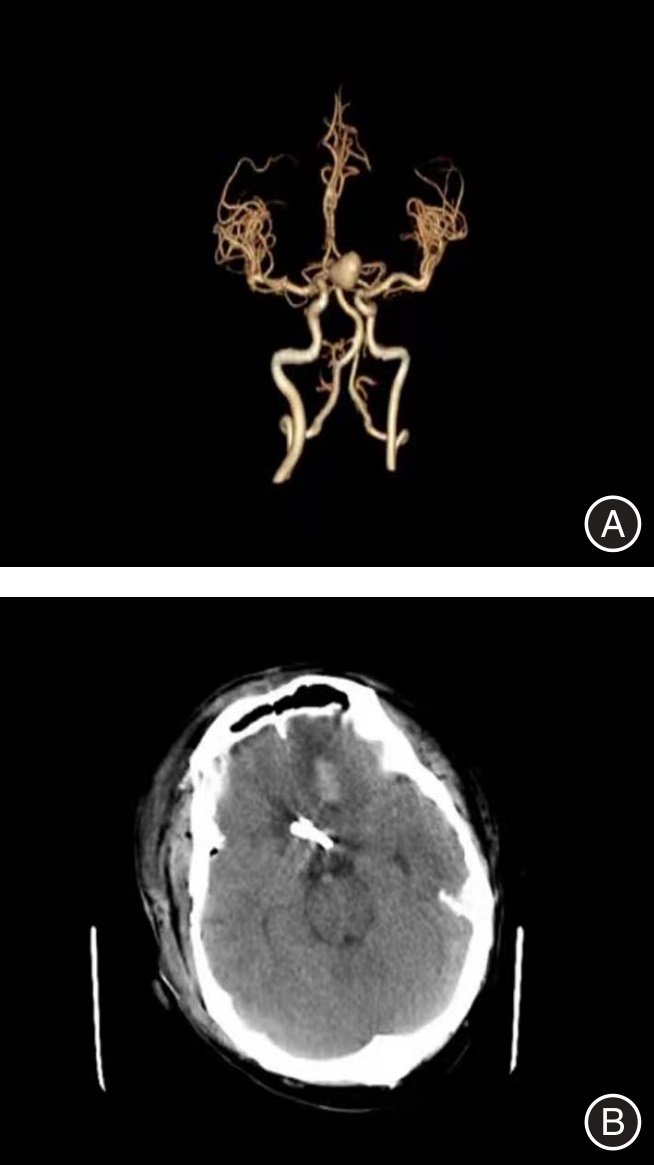

目的 探讨血清基质金属蛋白酶2(MMP-2)、髓过氧化物酶(MPO)、神经轴突导向因子3E(Sema3E)对全麻颅内动脉瘤夹闭术患者预后的预测价值。 方法 选取2023年5月至2025年5月张家口市第一医院收治125例全麻颅内动脉瘤夹闭术患者作为研究对象,根据术后1个月格拉斯哥预后评分(GOS),将1 ~ 3分的患者纳入预后不良组(29例),4 ~ 5分的患者纳入预后良好组(96例)。比较两组临床资料及血清MMP-2、MPO、Sema3E水平,并予以多因素logistic回归分析法分析全麻颅内动脉瘤夹闭术患者预后不良的危险因素,采用受试者工作特征(ROC)曲线分析血清MMP-2、MPO、Sema3E对全麻颅内动脉瘤夹闭术患者预后的预测价值,比较不同临床特征血清MMP-2、MPO、Sema3E水平,采用Spearman相关性分析血清MMP-2、MPO、Sema3E与临床特征的相关性。 结果 预后不良组Hunt-Hess分级Ⅲ级、术前GCS评分< 8分的患者占比为27.59%、51.72%,高于预后良好组的10.42%、5.21%(P < 0.05)。预后不良组血清MMP-2、MPO、Sema3E水平均高于预后良好组(P < 0.05)。血清MMP-2、MPO、Sema3E水平高是全麻颅内动脉瘤夹闭术患者预后不良的独立危险因素(OR = 1.087、2.807、2.079,P < 0.05)。血清MMP-2、MPO、Sema3E及联合检测预测全麻颅内动脉瘤夹闭术患者预后的曲线下面积(AUC)分别为0.747、0.690、0.656、0.809,诊断敏感度分别为72.41%、62.07%、68.97%、86.21%,特异度分别为72.92%、73.96%、66.67%、70.83%,其中联合检测的AUC最高(P < 0.05)。Hunt-Hess分级Ⅲ级患者血清MMP-2、MPO、Sema3E水平高于Ⅰ级、Ⅱ级患者,Ⅱ级患者高于Ⅰ级患者;术前GCS评分< 8分的患者血清MMP-2、MPO、Sema3E水平高于≥ 8分的患者(P < 0.05)。血清MMP-2、MPO、Sema3E与Hunt-Hess分级均呈正相关(r= 0.497、0.662、0.595,P < 0.05),与术前GCS评分均呈正相关(r = -0.547、-0.602、-0.697,P < 0.05)。 结论 全麻颅内动脉瘤夹闭术患者Hunt-Hess分级及术前GCS评分与预后具有一定联系,且血清MMP-2、MPO、Sema3E水平与Hunt-Hess分级、GCS评分密切相关,血清MMP-2、MPO、Sema3E水平高均为全麻颅内动脉瘤夹闭术患者预后不良的独立危险因素,且对患者预后具有较高预测价值,其中联合检测的预测价值最高。

Objective To explore the predictive value of serum matrix metalloproteinase-2 (MMP-2), myeloperoxidase (MPO), and axonal guidance factor 3E (Sema3E) in predicting the prognosis of patients undergoing intracranial aneurysm clipping surgery under general anesthesia. Methods A total of 125 patients who underwent general anesthesia for intracranial aneurysm clipping surgery at Zhangjiakou First Hospital from May 2023 to May 2025 were selected as the study subjects. Patients with Glasgow Outcome Scale (GOS) scores ranging from 1 to 3 one month after surgery were included in the poor prognosis group (29 cases), while those with scores from 4 to 5 were included in the good prognosis group (96 cases). The clinical data and the levels of serum MMP-2, MPO, and Sema3E were compared between the two groups. Multivariate logistic regression analysis was used to analyze the risk factors for poor prognosis in patients undergoing general anesthesia for intracranial aneurysm clipping surgery. Receiver Operating Characteristic (ROC) curves were employed to analyze the predictive value of serum MMP-2, MPO, and Sema3E for the prognosis of patients undergoing intracranial aneurysm clipping under general anesthesia. The levels of serum MMP-2, MPO, and Sema3E among patients with different clinical characteristics were compared. Spearman correlation analysis was conducted to investigate the correlation between serum MMP-2, MPO, and Sema3E and clinical features. Results The proportions of patients with Hunt-Hess grade Ⅲ and preoperative Glasgow Coma Scale (GCS) score < 8 in the poor prognosis group were 27.59% and 51.72%, respectively, which were higher than the 10.42% and 5.21% in the good prognosis group (P < 0.05). The levels of serum matrix metalloproteinase-2 (MMP-2), myeloperoxidase (MPO), and semaphorin 3E (Sema3E) in the poor prognosis group were higher than those in the good prognosis group (P < 0.05). High levels of serum MMP-2, MPO, and Sema3E were independent risk factors for poor prognosis in patients undergoing intracranial aneurysm clipping surgery under general anesthesia (OR = 1.087, 2.807, 2.079, P < 0.05). The areas under the curve (AUC) for predicting the prognosis of patients undergoing intracranial aneurysm clipping surgery under general anesthesia using serum MMP-2, MPO, Sema3E, and combined detection were 0.747, 0.690, 0.656, and 0.809, respectively. The diagnostic sensitivities were 72.41%, 62.07%, 68.97%, and 86.21%, and the specificities were 72.92%, 73.96%, 66.67%, and 70.83%, respectively. Among them, the AUC of combined detection was the highest (P < 0.05). The levels of serum MMP-2, MPO, and Sema3E in Hunt-Hess grade Ⅲ patients were higher than those in grade Ⅰ and Ⅱ patients, with grade Ⅱ patients having higher levels than grade Ⅰ patients. Patients with preoperative GCS scores < 8 had higher levels of serum MMP-2, MPO, and Sema3E than those with scores ≥ 8 (P < 0.05). Serum MMP-2, MPO, and Sema3E were positively correlated with Hunt-Hess grading (r = 0.497, 0.662, 0.595, 0.639, P < 0.05) and negatively correlated with scores of preoperative GCS (r = -0.547, -0.602, -0.697, -0.521, P < 0.05). Conclusions There was a certain correlation between Hunt-Hess grading, preoperative Glasgow Coma Scale (GCS) score, and the prognosis of patients undergoing intracranial aneurysm clipping surgery under general anesthesia. The levels of serum matrix metalloproteinase-2 (MMP-2), myeloperoxidase (MPO), and semaphorin 3E (Sema3E) were closely related to Hunt-Hess grading and GCS score. High levels of serum MMP-2, MPO, and Sema3E were independent risk factors for poor prognosis in patients undergoing intracranial aneurysm clipping surgery under general anesthesia and had high predictive value for patient prognosis. Among them, combined detection had the highest predictive value.